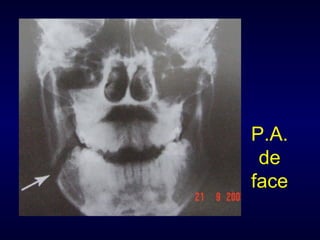

Exame Radiográfico Waters P.A. de face Perfil e perfil oblíquo Hirtz Towne com boca aberta Panorâmica Oclusal T.C.

P.A. de face